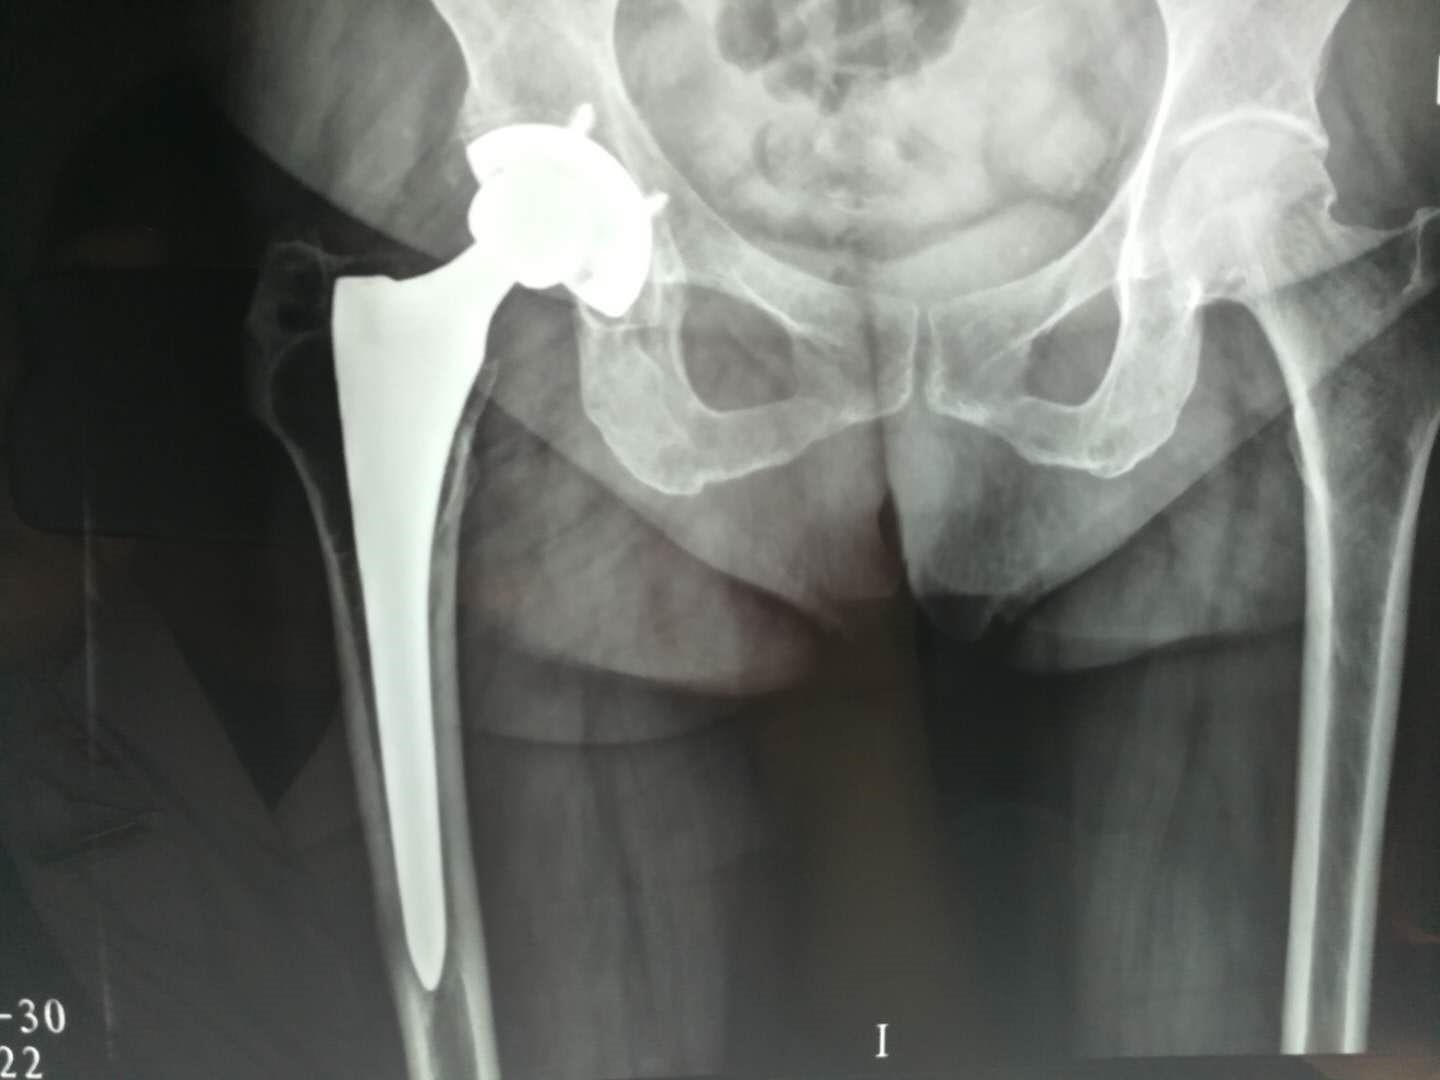

股骨头坏死分期的I、II、III期患者可以进行保髋治疗:包括减轻负重、高压氧治疗、脉冲电刺激治疗、高频冲击波治疗、药物治疗、保髋手术:髓芯减压、髓芯减压+干细胞移植、带血管蒂骨瓣移植术(带旋髂浅动脉髂骨瓣、带旋股外动脉横支大粗隆骨瓣)、粗隆间或股骨基底旋转截骨,IV、V期患者只能进行人工全髋关节置换手术治疗。

6.股骨头坏死到了什么程度必须换关节?

从X片上发现自己的股骨头不圆了,并且出现疼痛,这时可能要考虑换关节。而对于一些X片上显示股骨头不圆,却没有感到疼痛的患者,同时没有出现髋关节活动受限时可以暂时不换关节。换言之,只有当股骨头坏死导致出现骨关节炎,一活动就疼,影响到日常生活时,才需要做髋关节置换。

7.股骨头坏死患者做关节置换的最佳时机?

股骨头缺血性坏死的患者多为中青年,很多患者担心过早进行关节置换可能存在假体使用寿命的问题,但随着材料学的进步和手术技术的发展,目前的四代陶瓷对陶瓷界面全髋关节置换术后30年的假体生产率已经超过90%。同时人工关节没有自我更新及修复的能力,因此应该有“定期保养”的意识,但这种“保养”并不需要手术或吃药,只要患者每年拍摄一次髋关节的X光片,手术医生通过与术后即刻的X光对比就可以明确是否存在磨损及磨损的程度。在出现磨损征象的早期,只要通过简单的更换人工髋关节的衬垫就等于更换了一套全新的假体,不需要进行大翻修手术。

因此只要患者出现股骨头塌陷、关节疼痛症状影响生活或髋关节功能受限时就应该考虑进行进行人工全髋关节置换手术,尽快恢复正常生活,提高生活质量,保护髋关节功能。